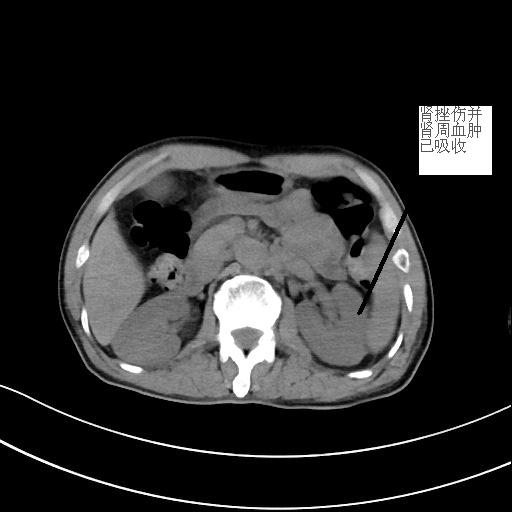

患者潘先生,因騎車摔倒入院搶救。入院時(shí),潘先生神志已模糊,無法對(duì)答,檢查檢驗(yàn)提示顱內(nèi)多發(fā)損傷,出現(xiàn)腦疝,病情危重,我院神經(jīng)外科團(tuán)隊(duì)緊急聯(lián)系福醫(yī)大附二院當(dāng)日值班專家來院開展開顱手術(shù)。經(jīng)及時(shí)搶救,患者病情穩(wěn)定,轉(zhuǎn)危為安。

<<<< 治療前后對(duì)比